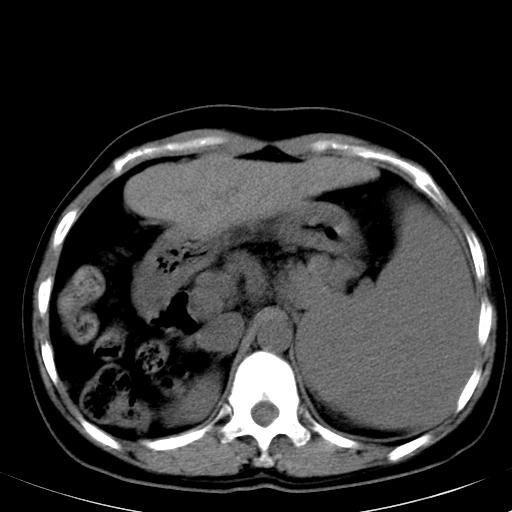

标题: CT19818:女40,脾大伴贫血,无肝炎病史 [打印本页]

标题: CT19818:女40,脾大伴贫血,无肝炎病史

巨脾。

肝硬化、门脉高压、脾大。再障+肝硬化促成巨脾。

左肝大/右肝小,脾大,考虑肝硬化门脉高压,脾大。  不知是否有血吸虫感染病史

肝叶比例失调,肝左叶明显增大,包膜欠规整,脾大,支持考虑肝硬化、门脉高压、脾大。